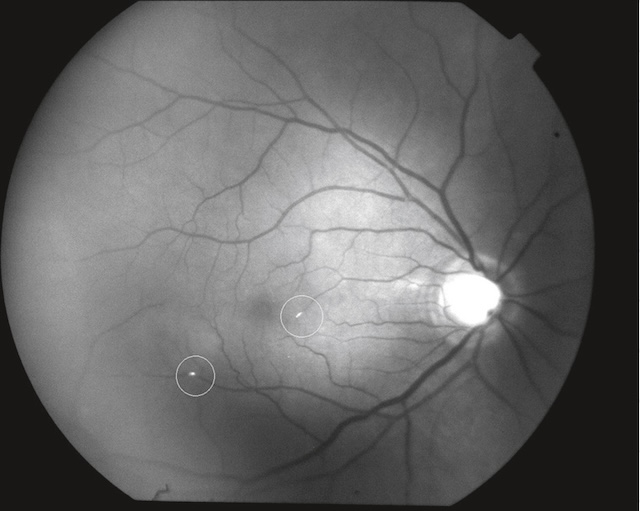

291Beaucoup plus rarement, il s’agit d’emboles lipidiques consécutifs à une fracture des os longs (« embolie graisseuse » se traduisant à l’examen du fond d’œil par des nodules cotonneux, fig. 16.9) ou d’emboles tumoraux (myxome de l’oreillette).

Lésions de petite taille, blanches, superficielles, d’aspect duveteux et à contours flous; chaque nodule correspond à une interruption du flux axoplasmique dans les fibres optiques secondaire à l’occlusion d’une artériole précapillaire. Il s’agit donc d’un signe d’ischémie localisée.

Ces deux photographies couleur du fond d’œil montrent plusieurs nodules cotonneux bien visibles, localisés à proximité de la papille optique. Sur l’image supérieure, les lésions blanches sont groupées en amas irréguliers le long des arcades vasculaires, contrastant nettement avec la rétine environnante. L’image inférieure confirme cette atteinte, avec des foyers cotonneux plus nombreux, éparpillés au-dessus et en dessous de la tête du nerf optique. L’aspect floconneux et blanchâtre de ces nodules traduit une ischémie focale des fibres nerveuses rétiniennes, fréquemment observée dans les rétinopathies hypertensives ou diabétiques.